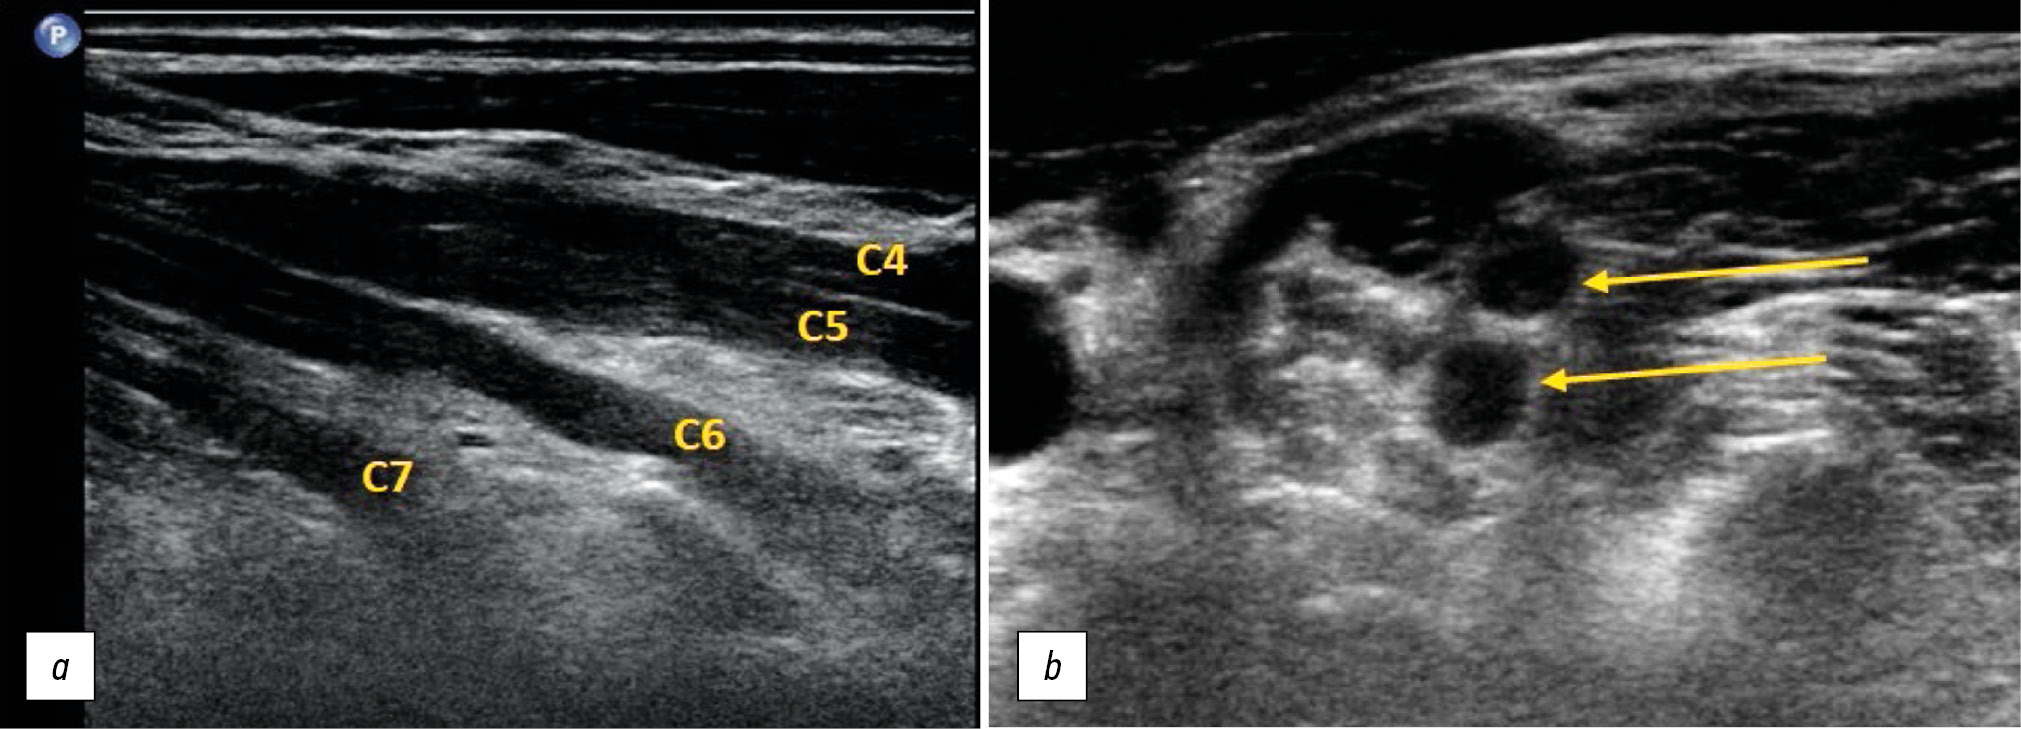

Characteristic changes in the structure of the brachial plexus, which are visible on US imaging and are characteristic of Parsonage–Turner syndrome, include thickening and decreased echogenicity of the ventral branches of the C5, C6, and C7 spinal nerves, the primary superior, and middle plexus trunks in the supraclavicular part of the plexus (Fig. 9).

Fig. 9. Ultrasound examination of Parsonage–Turner syndrome. Thickening of the ventral branches of the C5, C6, and C7 spinal nerves and the primary upper and middle trunks of the plexus (arrows). Longitudinal (a) and transverse (b) projections of the supraclavicular part of the brachial plexus.